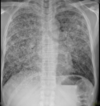

• Vertical Transmission during birth

* **CXR:** bilateral bihilar interstitial infiltrates * **High resolution CT**: If above nil then do these for cysts and nodules * **Bronchoscopy associated with bronchoalveolar lavage:** Use Grocott's stain and will show ‘mexican hat’ appearance. DIAGNOSTIC